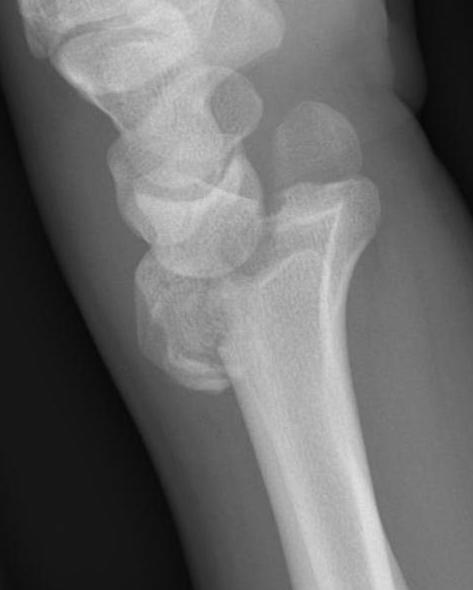

Dorsal distraction plating

Indication

Internal radiocarpal distraction

- unreconstructable distal radius fractures

- early weight bearing in poly trauma patients

- osteoporotic bone

Advantage - no pin site infection from external fixation

Disadvantage - need to remove plate at 3 - 4 months once fracture united

Technique

AO surgery foundation extended dorsal approach wrist

AO surgery foundation dorsal distraction plate

Arthrex dorsal spanning plate 2 incision video

Extended dorsal approach

- protect sensory radial nerve

- open 3rd extensor compartment / retract EPL radially

- mobilized 4th extensor compartment / retract EDC ulnarly

- bare area of radius proximally between EDC and ECRB / ECRL

Fixation to 2nd or 3rd metacarpal first

- 2nd metacarpal: under 2nd extensor compartment

- 3rd metacarpal: under 4th extensor compartment

- reduce / distract joint

- +/- additional radius fixation

Results

- systematic review of dorsal distraction plating

- 50% of wrist flexion extension compared to contralateral limb

- grip strength 80%